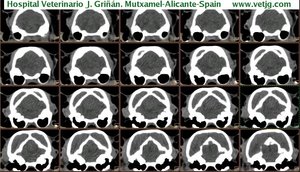

imágenes de TC en el gato | |||||||||||

Tomografía computarizada helicoidal |